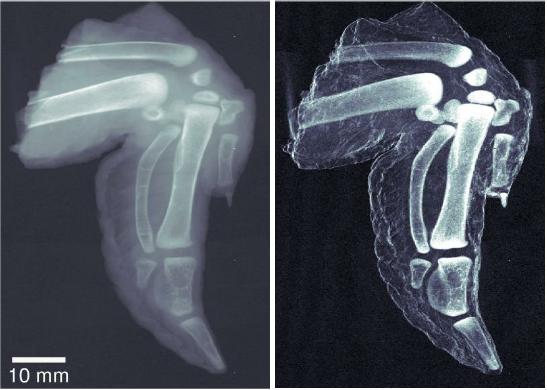

Unlike traditional x-ray images, which show a simple absorption contrast, dark-field images capture the scattering of the radiation within the material itself, exposing subtle inner changes in bone, soft tissue, or alloys. The overall clarity of the images is striking. The improved sensitivity in measuring bone density and hairline fractures could help diagnose the onset of osteoporosis. Because cancer or plaque cells scatter radiation slightly differently than normal cells, dark-field x-ray images can also be used to explore soft tissue, providing safer early diagnosis of breast cancer or the plaques associated with Alzheimer’s disease.